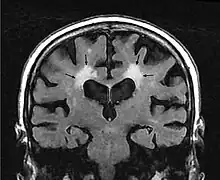

Leukoaraiosis is a particular abnormal change in appearance of white matter near the lateral ventricles. It is often seen in aged individuals, but sometimes in young adults.[1][2] On MRI, leukoaraiosis changes appear as white matter hyperintensities (WMHs) in T2 FLAIR images.[3][4] On CT scans, leukoaraiosis appears as hypodense periventricular white-matter lesions.[5]

The term "leukoaraiosis" was coined in 1986[6][7] by Hachinski, Potter, and Merskey as a descriptive term for rarefaction ("araiosis") of the white matter, showing up as decreased density on CT and increased signal intensity on T2/FLAIR sequences (white matter hyperintensities) performed as part of MRI brain scans.

These white matter changes are also commonly referred to as periventricular white matter disease, or white matter hyperintensities (WMH), due to their bright white appearance on T2 MRI scans. Many patients can have leukoaraiosis without any associated clinical abnormality. However, underlying vascular mechanisms are suspected to be the cause of the imaging findings. Hypertension, smoking, diabetes,[3] hyperhomocysteinemia, and heart diseases are all risk factors for leukoaraiosis.